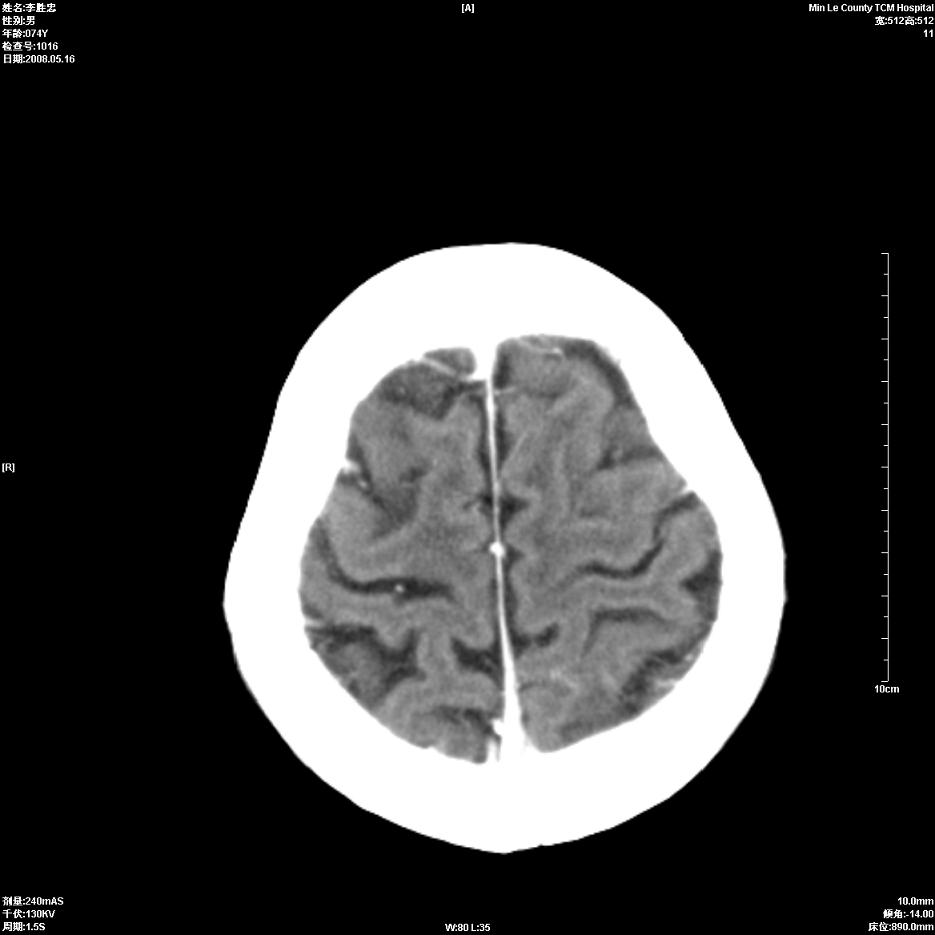

以下是引用深泽交通医院在2008-5-30 15:06:00的发言:[br]多发蛛网膜囊肿